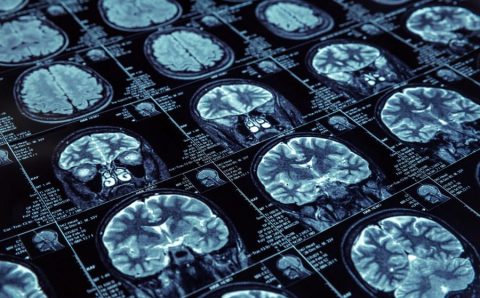

O que se sabe sobre as bases bioquímicas da doença de Alzheimer?

A doença de Alzheimer é uma enfermidade neurodegenerativa que afeta o cérebro, causando perda de memória, alterações no comportamento e dificuldades cognitivas. Embora as...